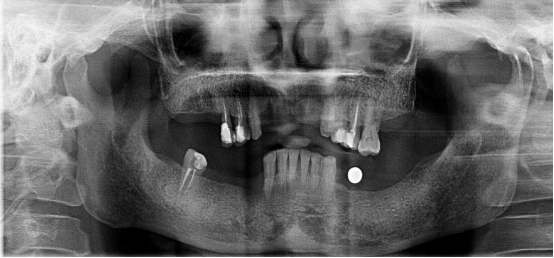

不連續(xù)性牙缺失修復(fù)案例

53歲的周女士家住福州晉安,由于患有嚴(yán)重的牙周炎導(dǎo)致牙齒沒剩下幾顆了。

“這邊缺一顆,那邊缺幾顆,這咬東西也太不得勁了,有牙齒跟沒牙齒一樣。”周女士深知牙齒缺失的痛苦,但是卻因?yàn)榻?jīng)濟(jì)的原因一直拖延沒有進(jìn)行牙齒修復(fù):“做牙齒多貴了,一顆就幾萬(wàn)塊哪里舍的?!?

錢雖然重要但缺失牙確實(shí)痛苦。而近期周女士又湊巧在報(bào)紙上看到科爾口腔的“敬業(yè)?!惫婊顒?dòng)的消息,一顆牙齒可以免費(fèi)領(lǐng)取4000元的種植牙紅包,優(yōu)惠力度之大前所未有,種植5顆還可以省下幾萬(wàn)塊。

周女士來院與劉斌元教授進(jìn)行交流后,劉斌元教授表示:“周女士缺失的牙齒是非連續(xù)性的,因此要種上好幾顆。牙齒缺失千萬(wàn)不可掉以輕心,長(zhǎng)時(shí)間缺失牙齒可造成牙槽骨萎縮,還會(huì)影響相鄰牙齒健康狀況”